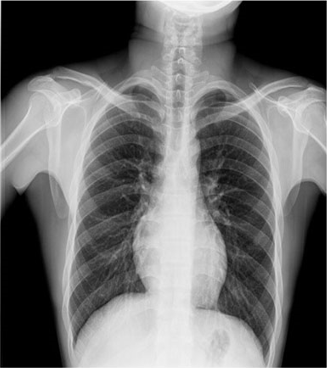

臨床圖片

微信圖片_20210927001112